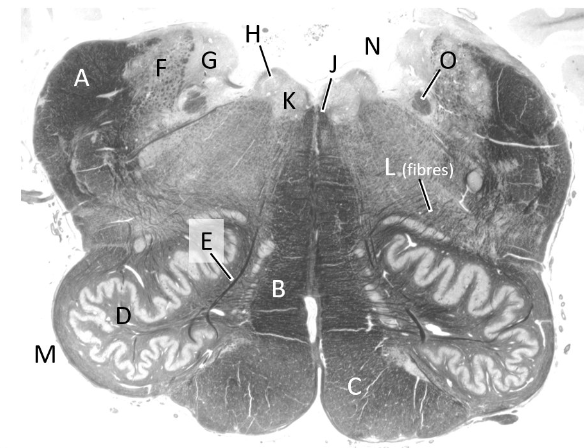

at what level is this?

lower medulla

what is a?

pyramid/ pyramidal tract (lm)

what is b?

spinal trigeminal nucleus (lm)

what is c?

trigeminal tract (lm)

what is d?

nucleus gracilis

what is e?

nucleus cuneatus (LM)

what is f?

internal arcuate fibres

what is g?

medial lemniscus (lm)

what is h?

inferior olivary nucleus (lm)